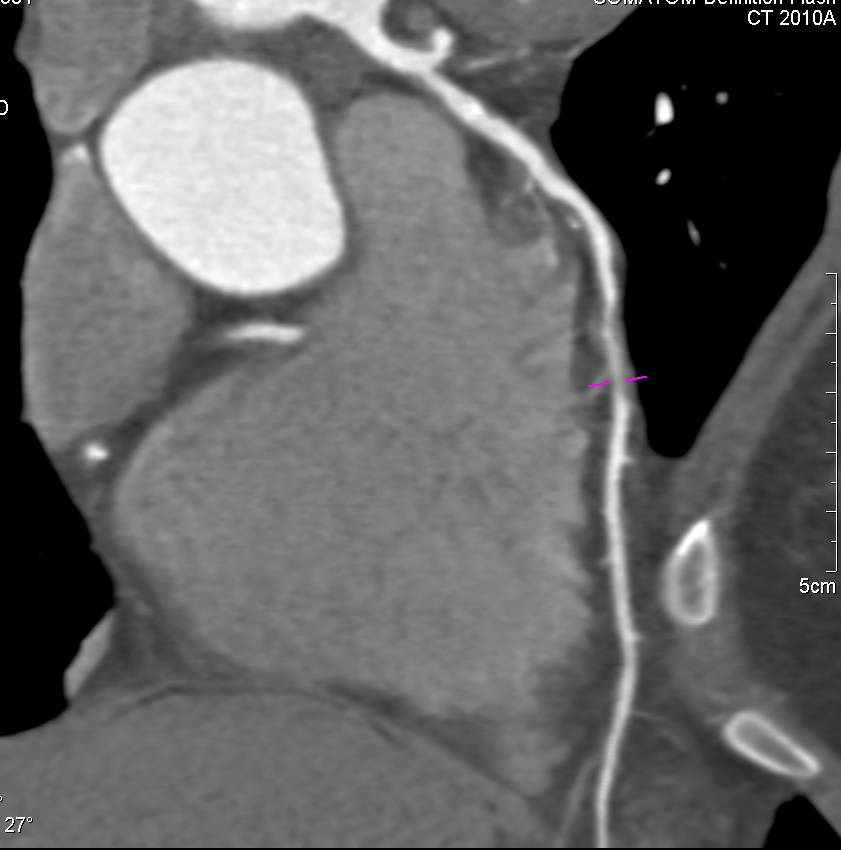

CCTA: Critical Right Coronary Artery (RCA) Stenosis in Multiple Views and Projections